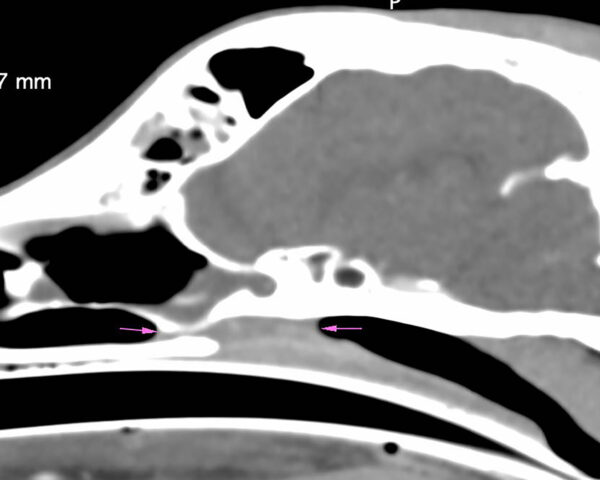

En la TC se apreciaron cambios óseos a nivel de las coanas, compatibles con una malformación congénita asociada o agravada por un posible proceso inflamatorio/infeccioso, que causaba una estenosis marcada de ambas coanas y del aspecto rostral de la nasofaringe (imágenes 1, 2 y 3). Entre los diagnósticos diferenciales de dicha estenosis de tejido blando se incluyeron: un proceso inflamatorio grave o un granuloma infeccioso (principalmente fúngico) sin que se pudiera descartar la presencia de una neoplasia nasofaríngea.

Imágenes 2 y 3. Las flechas rojas indican la lisis completa del tabique nasal en su porción media y la comunicación entre ambas cavidades nasales y las flechas verdes muestran la lisis de cornetes nasales y etmoidales.